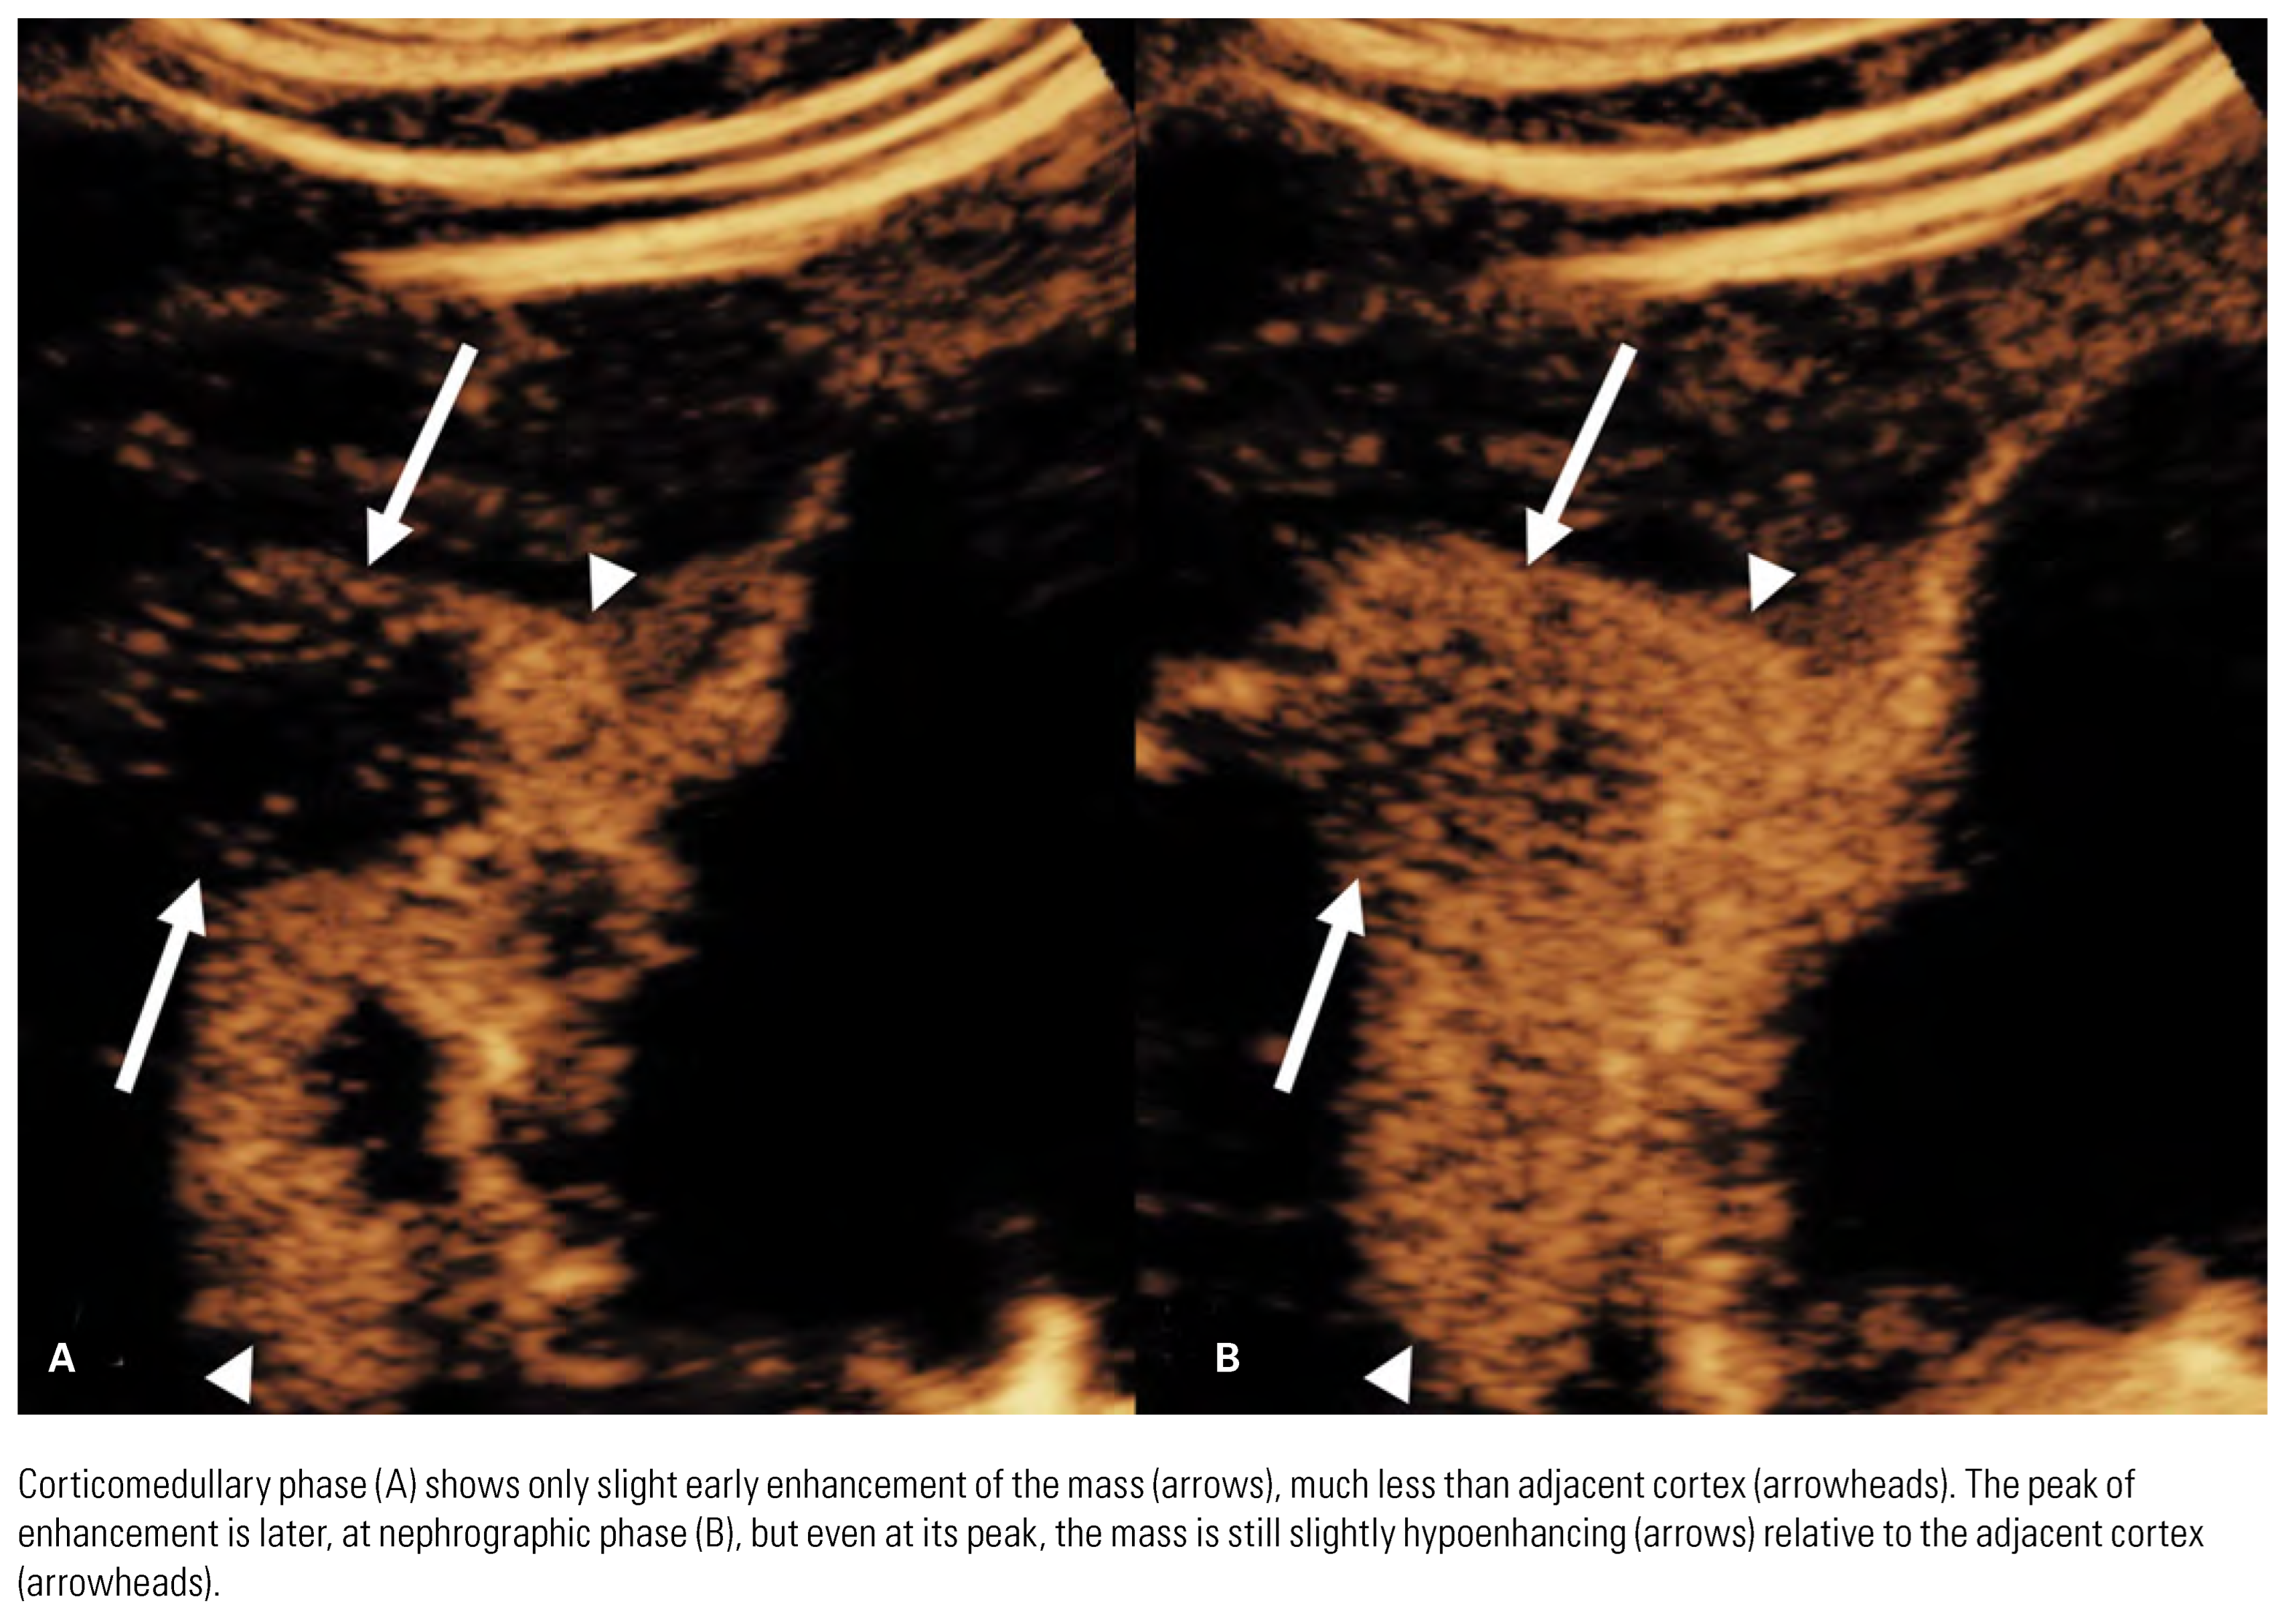

![]() |